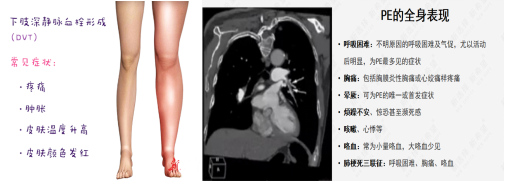

以肺血栓栓塞癥(PTE)為主要臨床類型的肺栓塞(PE)和深靜脈血栓形成(DVT)合稱為靜脈血栓栓塞癥(VTE),是同一疾病在不同階段、不同部位的兩種重要臨床表現形式。臨床上諸多科室的患者均存在VTE風險,其發(fā)病隱匿、臨床癥狀不典型,容易誤診、漏診,一旦發(fā)生,致死和致殘率高; DissolVE-2 研究表明[1],我國的外科住院患者 VTE 中、 高風險比例高達86.1%,內科患者 VTE 高風險比例為 36.6%;文獻報道美國每年死于VTE患者25萬至30萬。除了死亡之外,未能及時處理的VTE,多數不能幸免于深靜脈血栓后遺癥(PTS)的發(fā)生,造成患者長期病痛,影響生活和工作能力,嚴重者可致殘。

下肢深靜脈血栓(DVT)的觀察及護理:

患肢體位患肢宜高于心臟平面20~30cm,可促進靜脈回流并降低靜脈壓,減輕疼痛與水腫。每日測量并記錄下肢周徑變化,以了解治療效果。術后鼓勵病人盡早活動,以免再次血栓形成。

肺栓塞(PE)的觀察及護理:

下肢DVT最嚴重的并發(fā)癥是肺栓塞。肺栓塞急性期病人應絕對臥床休息10~14天,床上活動時避免動作幅度過大,禁止按摩、擠壓或熱敷患肢,保持大便通暢,避免屏氣用力的動作,以防血栓脫落。若病人出現胸痛、呼吸困難、血壓下降等異常情況,提示可能發(fā)生肺栓塞,應立即囑病人平臥,避免做深呼吸、咳嗽、劇烈翻動,同時給予高濃度氧氣吸入,并報告醫(yī)師,配合搶救。